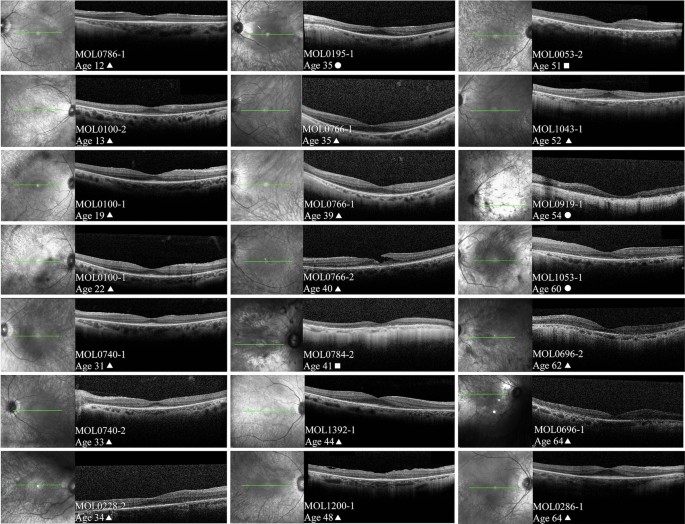

OCT imaging was available for 82 patients and foveal scans from 19 of them are presented according to patient age in Fig. 4. In two patients, OCT scans 3 years (MOL0100-1) and 4 years (MOL0766-1) apart are shown. In general, increased thinning of the photoreceptor layer (outer nuclear layer, ONL) occurs with age, with relative preservation of the ONL and ellipsoid zone (EZ) in the foveal area. Towards and above the age of 50, only a thin layer of photoreceptors is seen in the fovea, there is loss of the EZ, and in some cases this progresses to foveal atrophy (for example, patient MOL0919-1). In many cases (74 out of 82 patients) thickening of the inner limiting membrane or a fine epiretinal membrane (ERM) was observed in at least one eye, although often not in the foveal area, and not to the degree that necessitates surgical intervention. A lamellar macular hole was noted in one eye of MOL0766-2 at the age of 40. Interestingly, cystoid foveal and macular changes seem to be quite rare in FAM161A patients: small intraretinal cysts were identified in only 4 out of the 82 patients for whom OCT imaging was available, and frank cystoid changes were not observed at all.

Representative OCT (ocular coherence tomography) images. Infrared imaging of the macular area and OCT scans passing through the fovea from 19 patients with FAM161A-related retinal degeneration are shown, arranged according to patient age. In two patients, OCT scans that are 3 years (MOL0100-1) and 4 years (MOL0766-1) apart are presented. In general, increased thinning of the photoreceptor layer and loss of intact ellipsoid zone width occurs with age, with relative preservation in the foveal area. Above the age of 50, progression to foveal atrophy can be observed in some cases (for example, patient MOL0919-1). Interestingly, cystoid macular changes seem to be quite rare in FAM161A patients. Patient numbers, age at time of imaging and genotype are specified on each of the panels (triangles represent homozygousity for the frameshift mutation, squares homozygosity for the nonsense mutation and circles denote compound heterozygous patients).